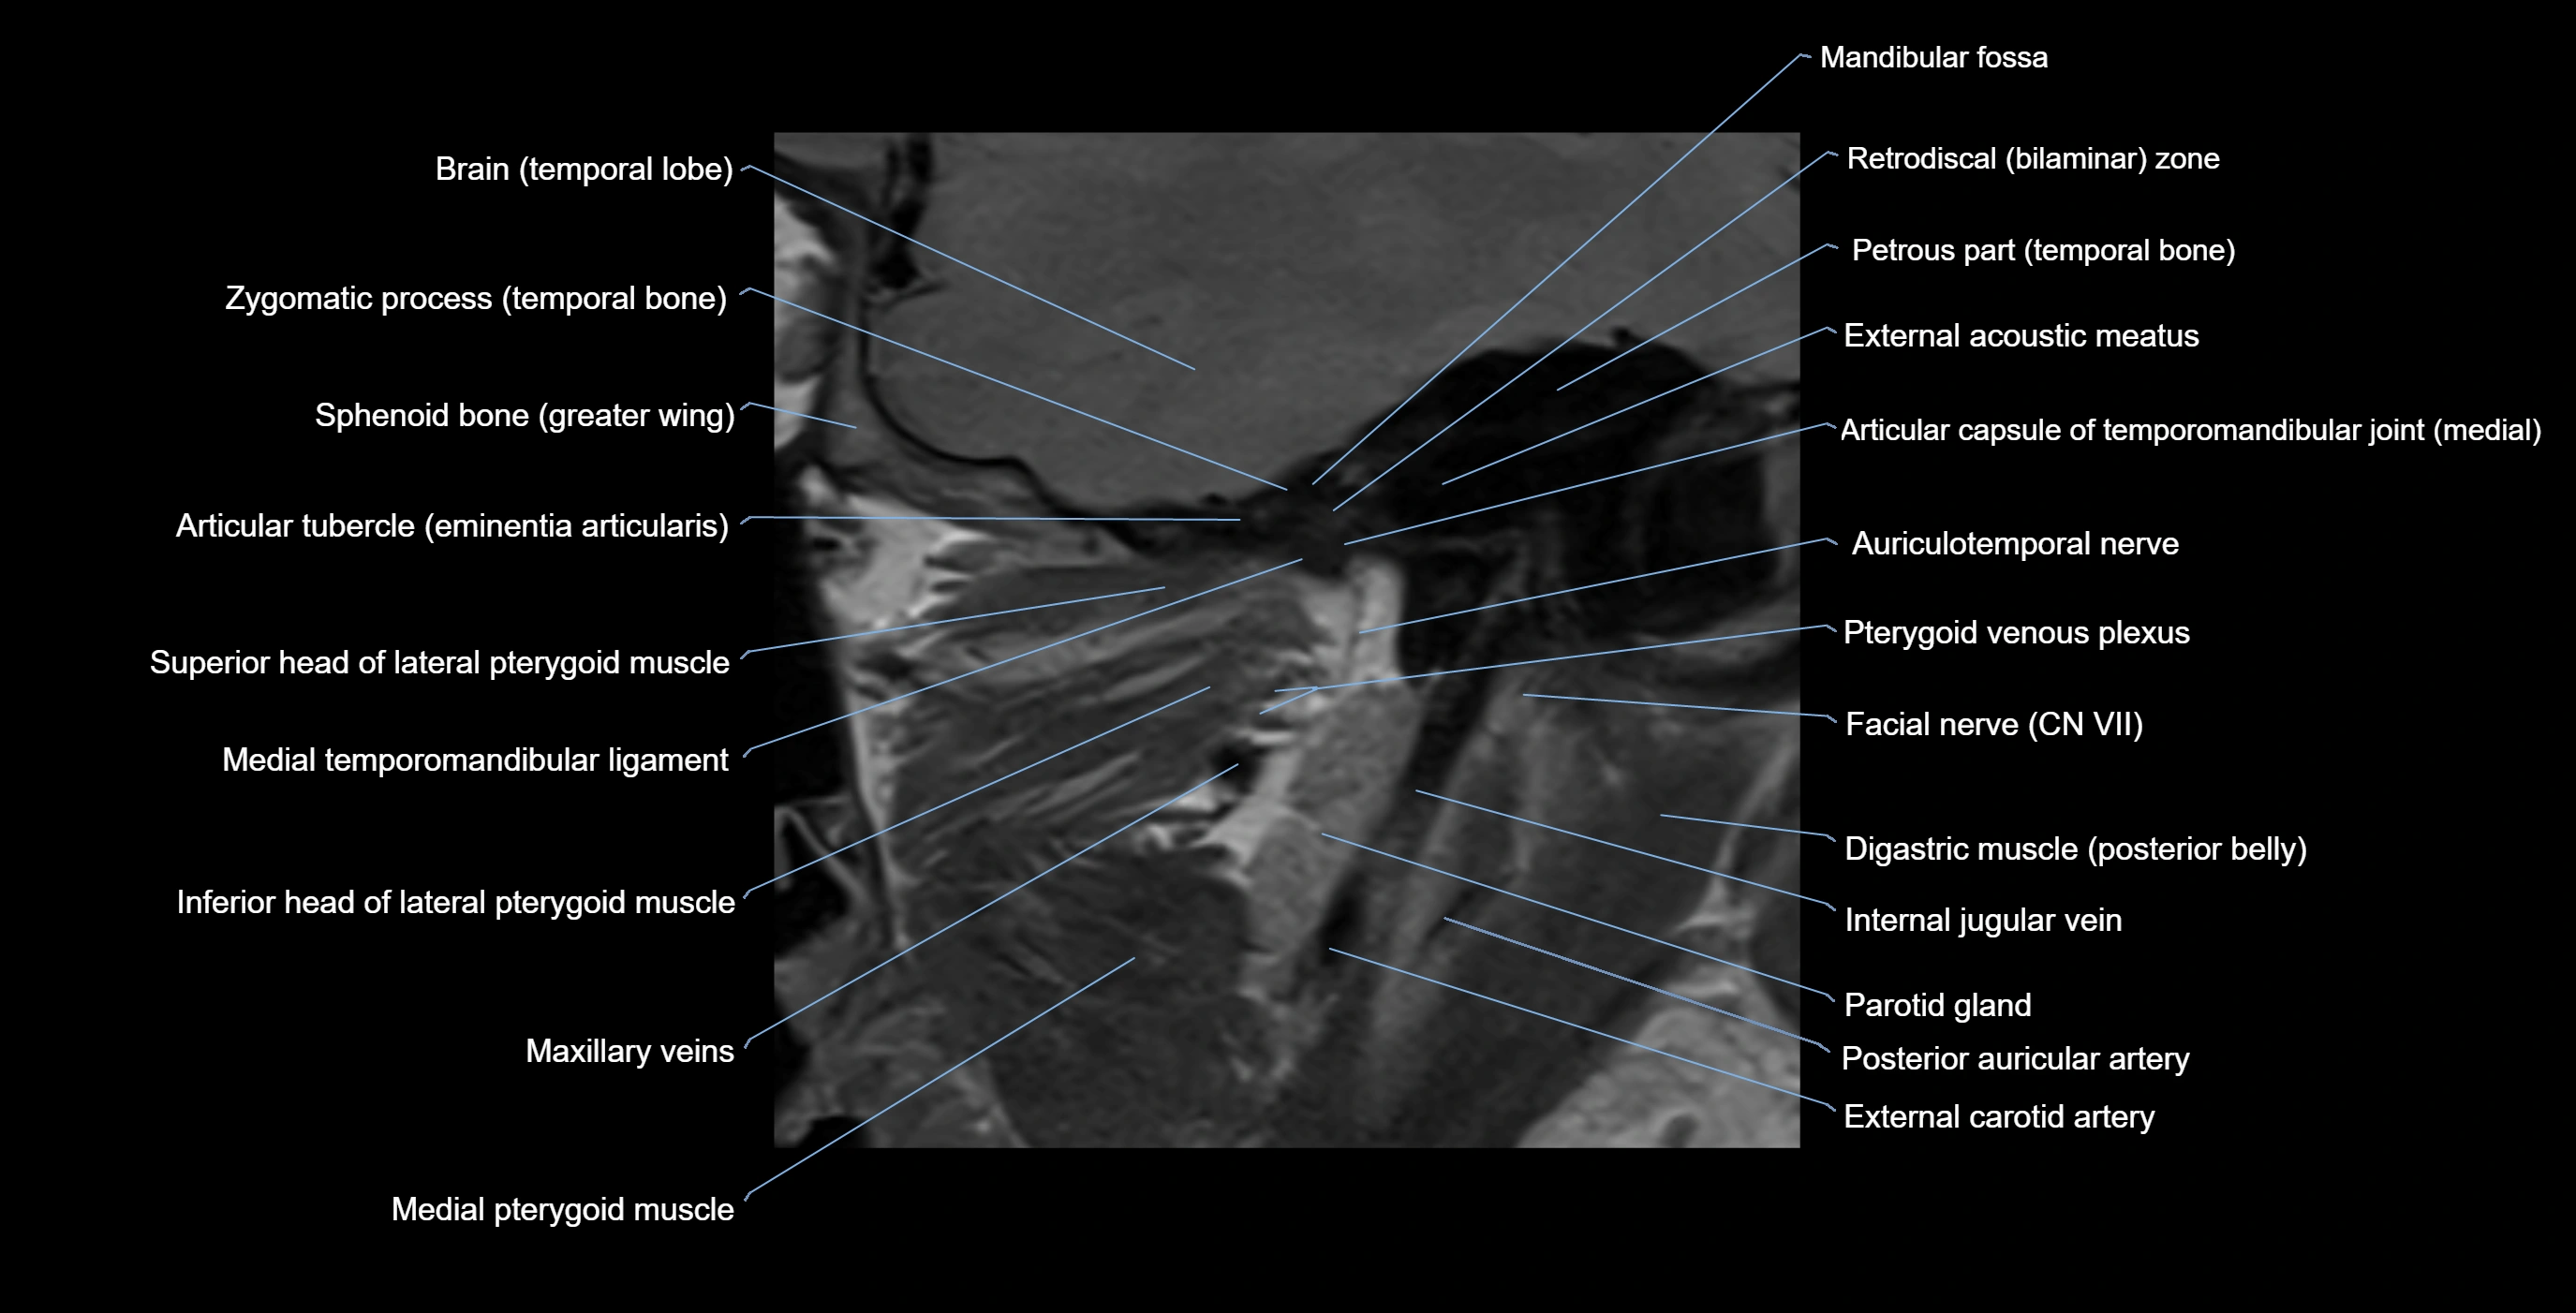

MRI appearance

T1-weighted images:

• Cortical bone: Low signal intensity

• Cancellous marrow: Intermediate to high signal depending on fatty content

• Teeth: Signal void structures

• Adjacent soft tissues: Normal gingiva and oral mucosa signal

T2-weighted images:

• Cortical bone and teeth: Low signal

• Marrow: Intermediate signal